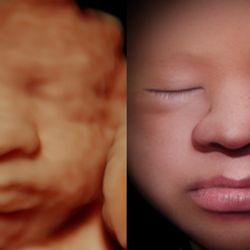

Check Ups Tests And Scans Available During Your Pregnancy Pregnancy Birth And Baby